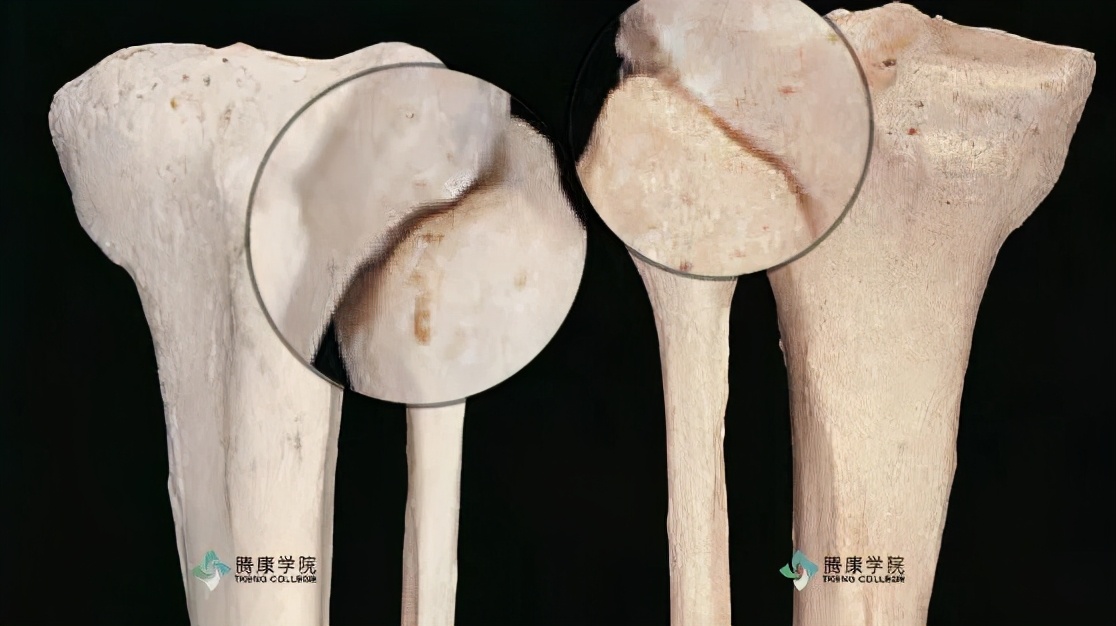

半月板撕裂是膝关节最常见的损伤,在运动员和一般人中发生的相对频繁。基本上,半月板撕裂通常与股骨髁有力的轴向扭转有关。受压膝关节内的轴向扭转可以对半月板进行挤压,并使其移位。移位或折叠的半月板会在力学上阻碍膝关节的运动。

内侧半月板受损伤的概率是外侧半月板的两倍。内侧半月板撕裂的损伤机制通常涉及绕轴旋转,也可能会涉及施加在膝关节外侧的外力。该力通常被描述为“外翻力”, 它可以导致膝关节的外翻位置,以及随后被施加在内侧副韧带与后内侧囊上的很大应力。由于内侧半月板与这些结缔组织之间的解剖*联学**系,传递至膝关节的巨大外翻力可以间接限制并进而损伤内侧半月板。

如果膝关节存在异常对位或有韧带不稳定病史,半月板撕裂的风险会加大,这种情况在前交叉韧带最为明显。